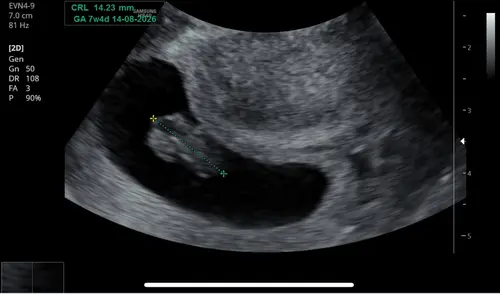

Vandaag een herhaal vitaliteitsecho gehad. Omdat ik 2 weken terug al 7+2 weken dacht te zijn bij de eerste vitaliteitsecho, maar werd teruggezet naar 6+2 weken. Voor mijn eigen gemoedsrust kreeg ik vandaag nog een herhaling. Nu bleek ik toch bijna 9 weken te zijn. Super blij en opgelucht. 🫶🏼🩵🩷